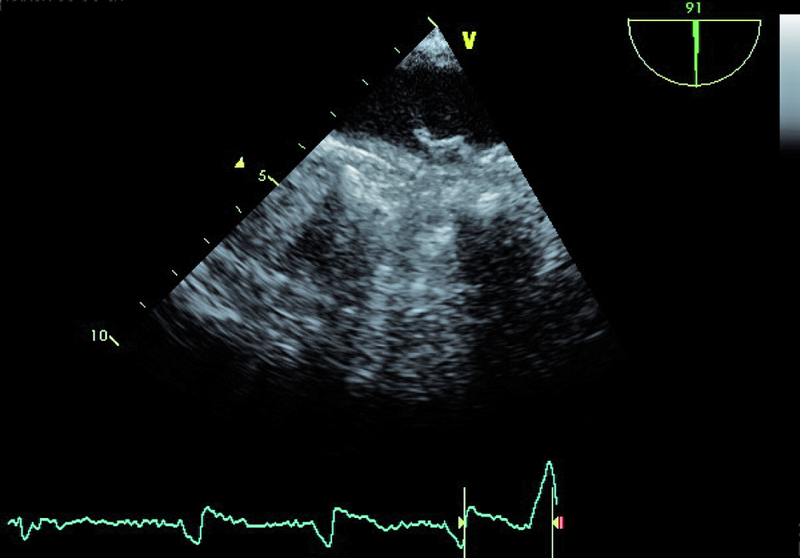

Mężczyzna, lat 68. Jakie patologie można rozpoznać na rycinach?

1. Powiększenie jamy lewej komory (ryc. 1).